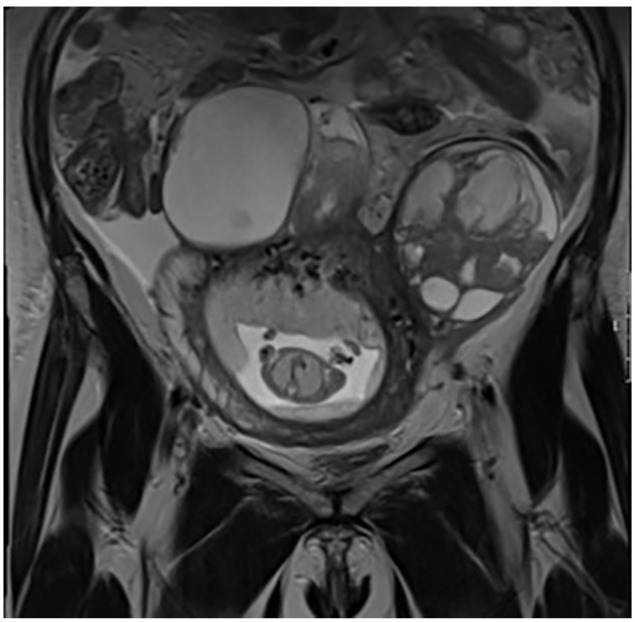

一名 43 岁女性在妊娠 14 周时出现失血和持续腹痛。超声波检查和随后的磁共振成像(MRI)显示双侧子宫附件多囊。在妊娠 17 周时进行了探查性开腹手术,诊断出双侧浆液性卵巢腺癌 FIGO IIIC 期。当时无法进行完全的细胞减灭术(CRS)。剖腹探查术后九天,胎膜早破和宫缩发生,她在妊娠 19 周后产下一名早产男婴。胎盘病理检查显示,她的卵巢癌转移到了胎膜上。我们描述了首例卵巢癌转移至胎盘胎膜蜕膜的病例,并进行了组织学、免疫组化和分子学确认。该病例强调了对罹患卵巢癌的孕妇认真评估胎盘和胎膜的重要性。

A 43-year-old female presented with blood loss and persistent abdominal pain at 14 weeks of gestation. Ultrasound examination and subsequent magnetic resonance imaging (MRI) revealed bilateral multicystic uterine adnexa. Exploratory laparotomy was performed at 17 weeks of gestation and bilateral serous ovarian adenocarcinoma FIGO stage IIIC was diagnosed. Complete cytoreductive surgery (CRS) was not feasible at that moment. Nine days after the exploratory laparotomy, immature rupture of membranes and contractions occurred and she delivered a premature boy after 19 weeks of gestation. Pathological examination of the placenta revealed that her ovarian cancer metastasized to the membranes. We describe the first case of ovarian cancer metastasized to the decidua of the placental membranes with histological, immunohistochemical, and molecular confirmation. This case highlights the importance of conscientious evaluation of placenta and membranes in pregnant women with ovarian cancer.